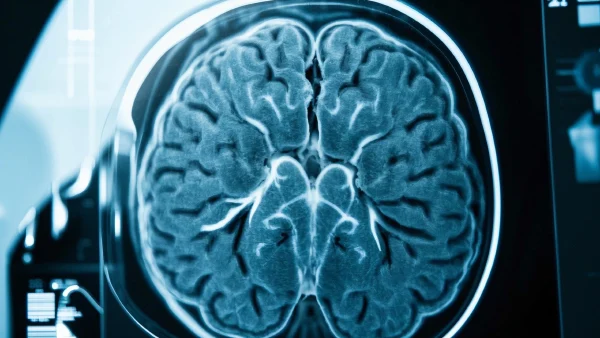

04. MRI是怎么帮忙诊断脑梗死的?

走进医院,医生很可能第一时间会建议做MRI(磁共振成像)。这种检查在目前已经成为诊断脑梗死的有效工具,因为它能在没有放射线的情况下,清清楚楚地看到大脑内部结构和病变部位。MRI就像“照妖镜”,可以区分新旧病变、面积大小,还能判断梗死的是哪一片脑组织,从而决定治疗方案。

有研究表明,早期MRI的诊断准确率高于CT,能更快提供关键信息。

05. MRI下的脑梗死:急性期到底能看到什么?

在急性脑梗死发生的头几天内,大脑受到损伤的那片区域,会因为缺氧而肿胀,MRI的片子上,医生常看DWI(弥散加权成像)序列,如果这块区域出现明显的高信号,那就初步判断有新近梗死点出现,同时肿胀往往会导致周边结构变形。

- 高信号区域形态有点像一块被泡胀的海绵,边缘不清

- 局部脑沟变浅,附近组织轻度移位

- DWI对应T2序列,往往也能看出亮度变化